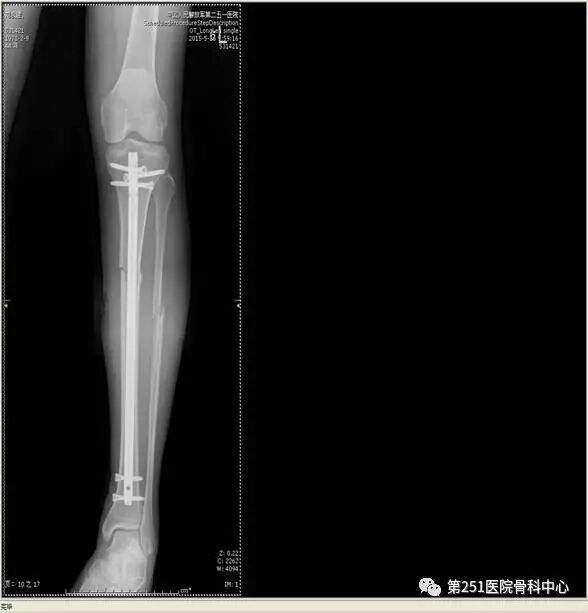

病例2:男性,44岁,车祸伤,双侧胫腓骨骨折(左侧)。

![]()